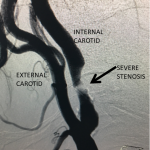

Figure 2.

Catheter angiography prior to angioplasty revealed critical stenosis (Figure 2). Angioplasty was therefore performed under local anesthesia with an embolic protection device deployed to catch any dislodged debris (Figure 3). After angioplasty, a stent was opened across the lesion to maintain long-term patency (Figure 4). Post-stent angiography showed smooth dilatation of the lesion. The patient’s aphasia continued to improve at his 6-week follow-up visit and duplex revealed no significant stenosis through the stent.